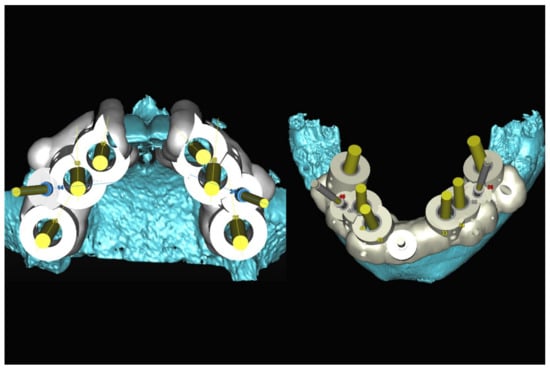

Figure 32.

Planning of the number, the diameter, the axis of the implants with respect to the design of the final prosthesis and the trajectory of the inferior alveolar nerves.

Figure 33.

Virtual stereolithographic surgical drilling guides designed according to the implant position.